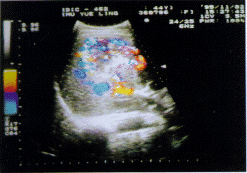

图2A 肝右叶S5段见55mm×38mm肿块,回声较强且

不均匀,血供丰富,呈篮网状

图2B 癌细胞排列成梁索状和巢状,巢间可见较多的小动脉、淋巴管及淤血扩张的小静脉,部分小静脉内可见癌栓形成,(HE 4×3.3)

图2 中分化肝细胞性肝癌